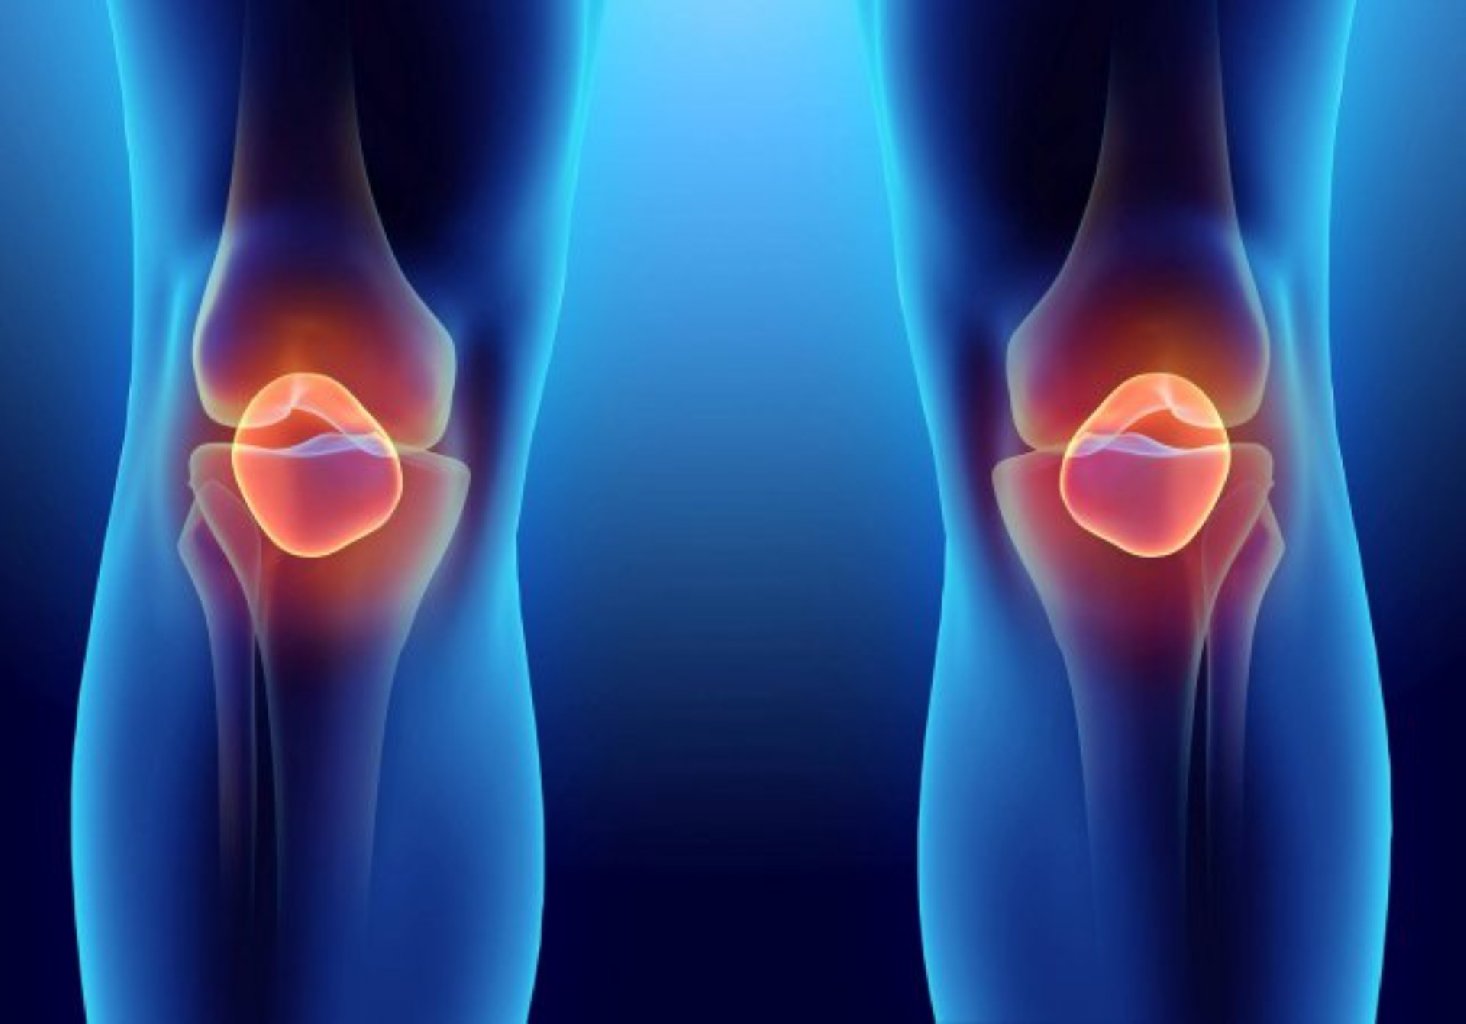

Diz artroplastiyası nədir? Diz artroplastiyası diz oynağında zədələnmiş və ya degenerativ toxumal ...